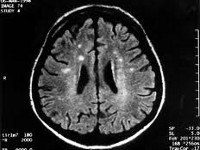

A81.0 Болезнь Крейтцфельдта-Якоба